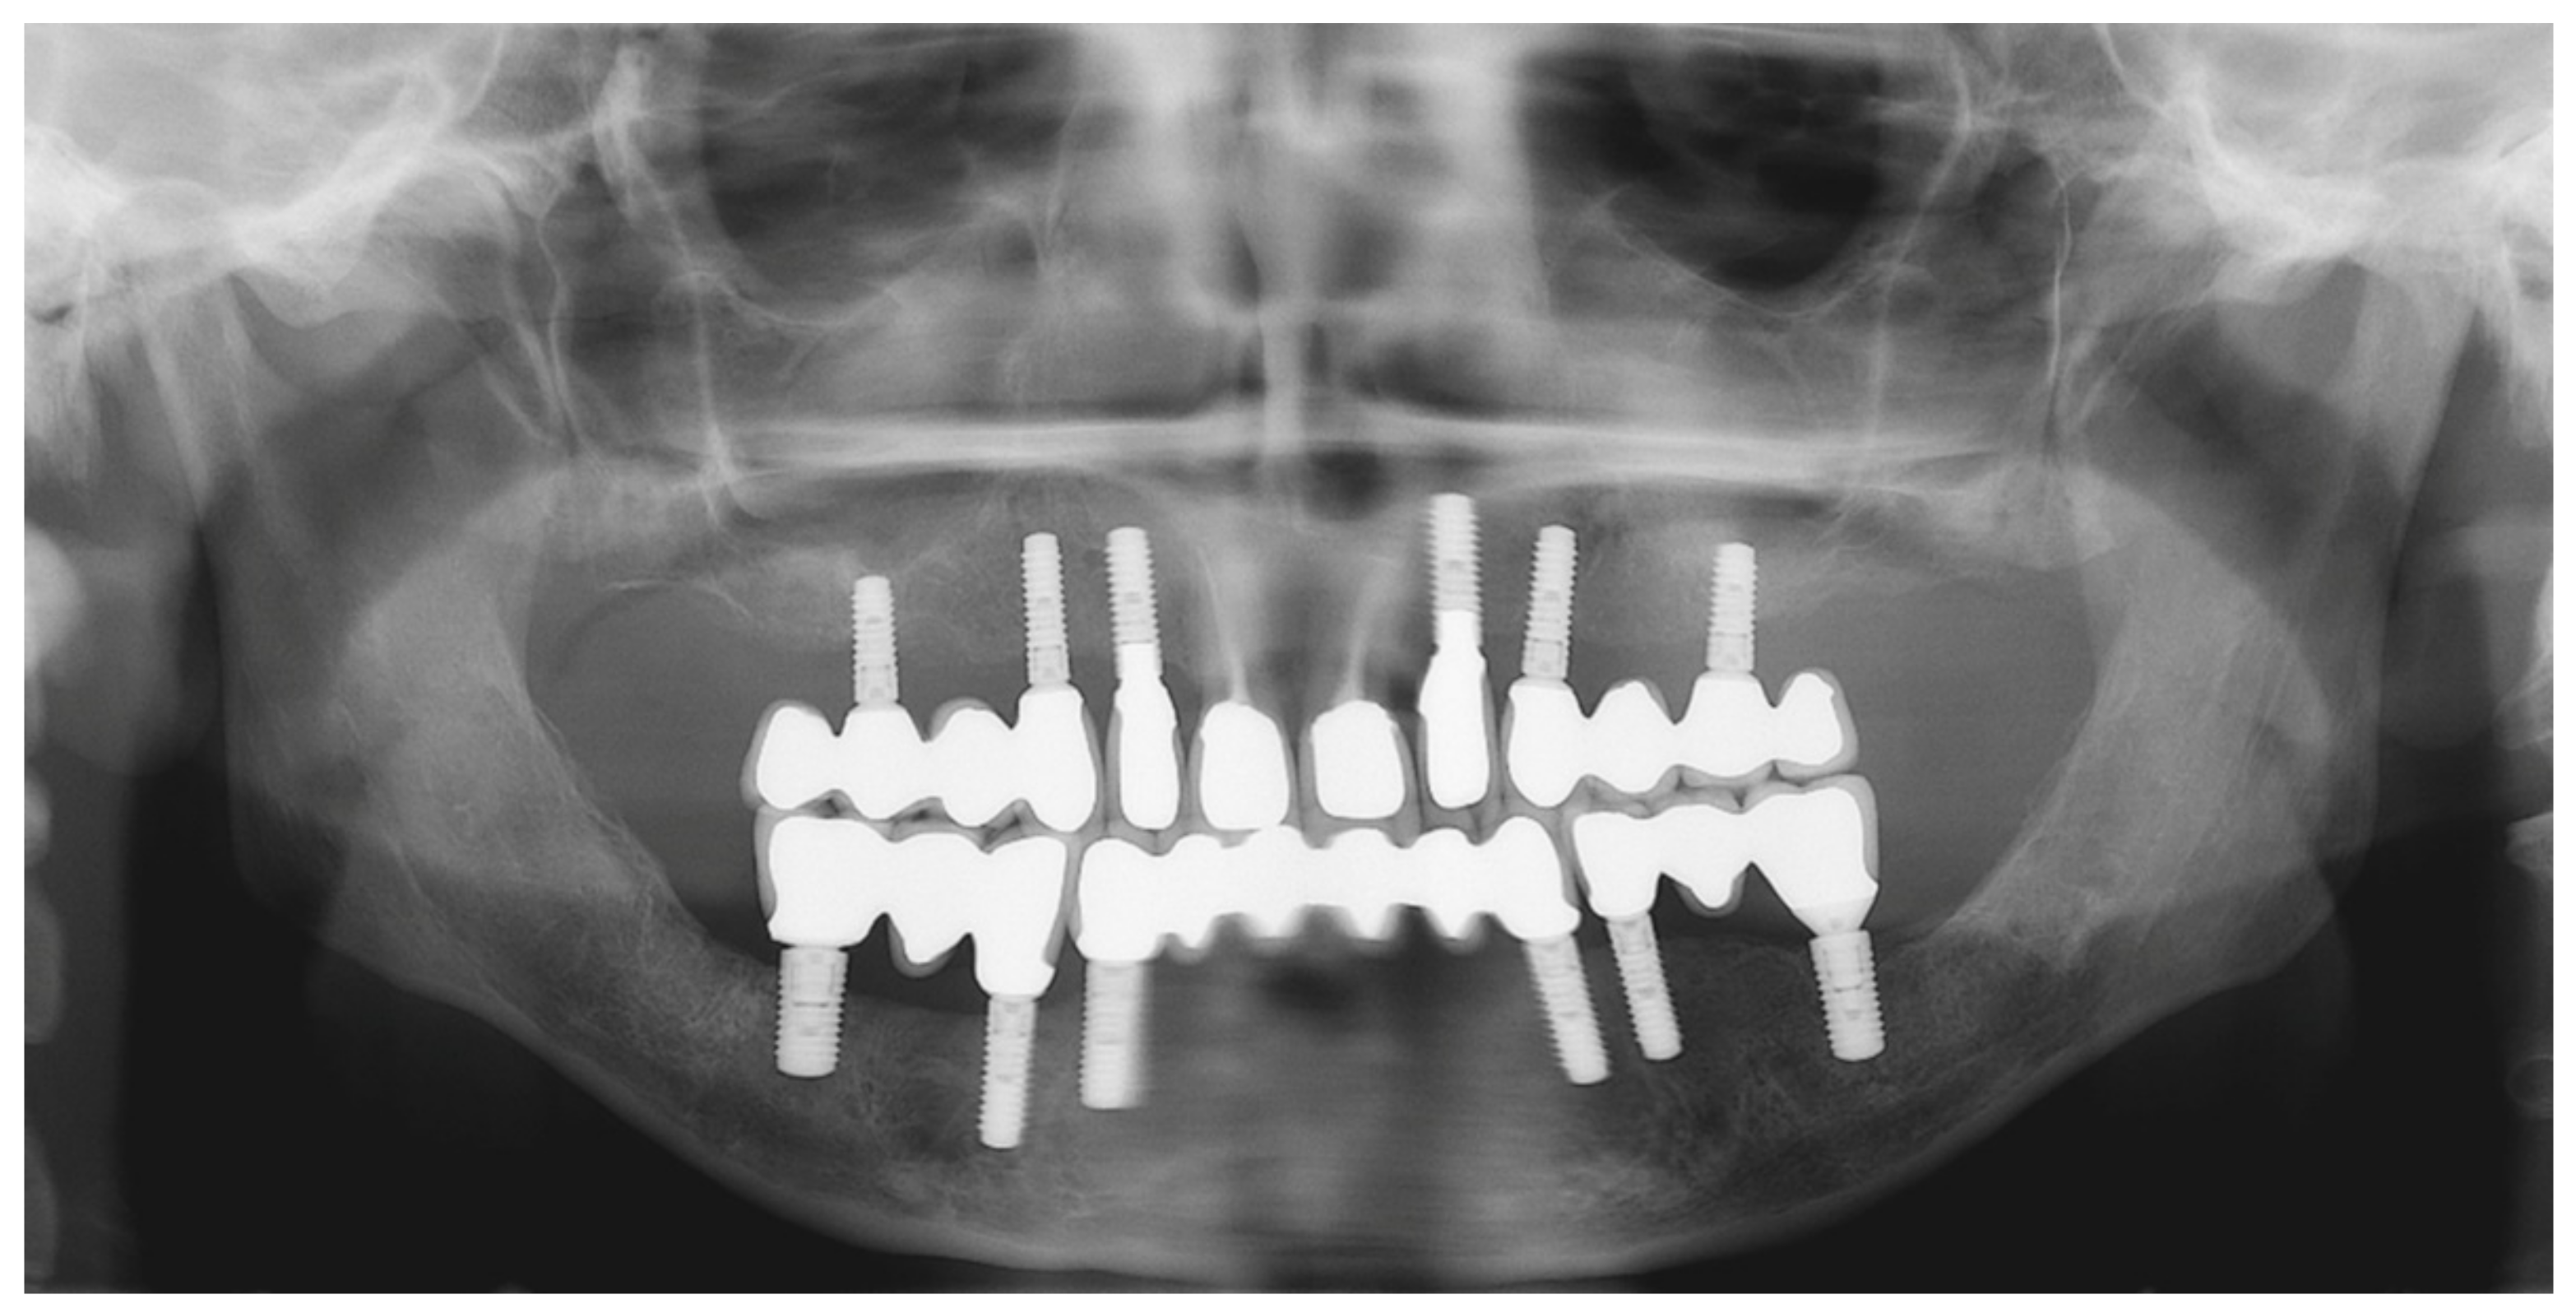

6.2.5. Postoperative (2-Years Follow-Up) Documentation:

6.3.5. Postoperative (3-Years Follow-Up) Documentation: